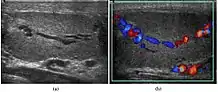

At ultrasound, the findings of acute epididymitis include an enlarged hypoechoic or hyperechoic (presumably secondary to hemorrhage) epididymis [Fig. 20a]. Other signs of inflammation such as increased vascularity, reactive hydrocele, pyocele and scrotal wall thickening may also be present. Testicular involvement is confirmed by the presence of testicular enlargement and an inhomogeneous echotexture. Hypervascularity on color Doppler images [Fig. 20b] is a well-established diagnostic criterion and may be the only imaging finding of epididymo-orchitis in some men.

Doppler ultrasound of epididymitis, seen as a substantial increase in blood flow in the left epididymis (top image), while it is normal in the right (bottom image). The thickness of the epididymis (between yellow crosses) is only slightly increased (7 mm).

Doppler ultrasound of epididymitis, seen as a substantial increase in blood flow in the left epididymis (top image), while it is normal in the right (bottom image). The thickness of the epididymis (between yellow crosses) is only slightly increased (7 mm). Doppler ultrasound of the scrotum of the same case, in the axial plane, showing orchitis (as part of epididymo-orchitis) as hypoechogenic and slightly heterogenic left testicular tissue (right in image), with an increased blood flow. There is also swelling of peritesticular tissue.

Doppler ultrasound of the scrotum of the same case, in the axial plane, showing orchitis (as part of epididymo-orchitis) as hypoechogenic and slightly heterogenic left testicular tissue (right in image), with an increased blood flow. There is also swelling of peritesticular tissue.